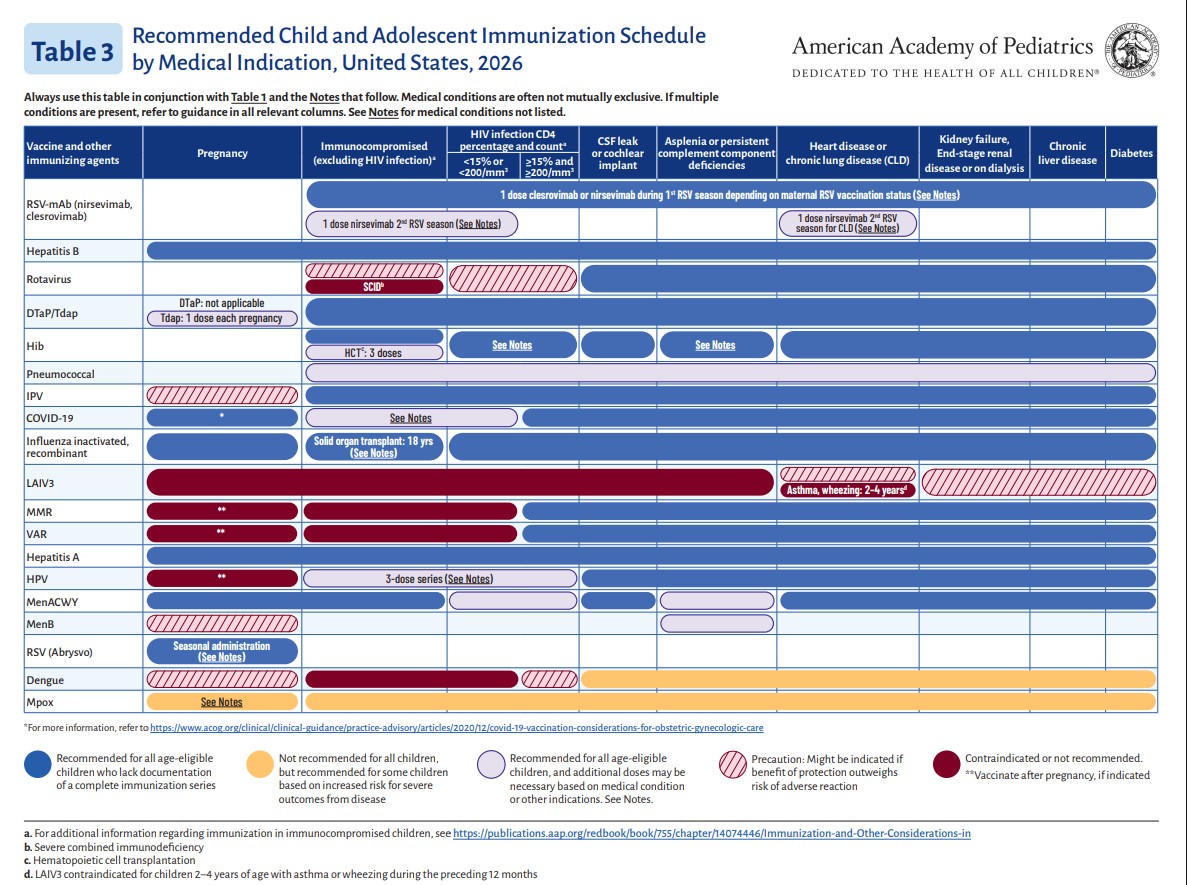

p 4